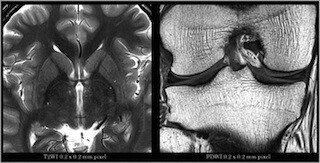

東芝メディカルシステムズは11月28日、MRI装置「Vantage Titan 3T」の新オプション「Saturn Gradient」を発表した。

同オプションにより、オープンボアでは困難だった傾斜磁場の安定した高出力化を実現した。また、最新ソフトウェア「M-Power V2.5」の搭載により、画質(Quality)、時間効率(Speed)、検査適応(Flexibility)をさらに高め、質の高い検査を提供するとしている。

具体的には、「Saturn Gradient」では、傾斜磁場出力の増加や大口径化に伴う、傾斜磁場コイルの"発熱"、"振動"、"送信効率"に着目。冷却機能を従来の2倍に増加させ、高負荷時の温度上昇を抑え中心周波数を一定に保つ。また、出力増加に伴い増大するローレンツ力を抑制する。さらに、高分解能撮像時でも安定した画像を得ることが可能となるだけでなく、撮像時の騒音も抑えた。加えて、新しいSAR低減技術を採用した。